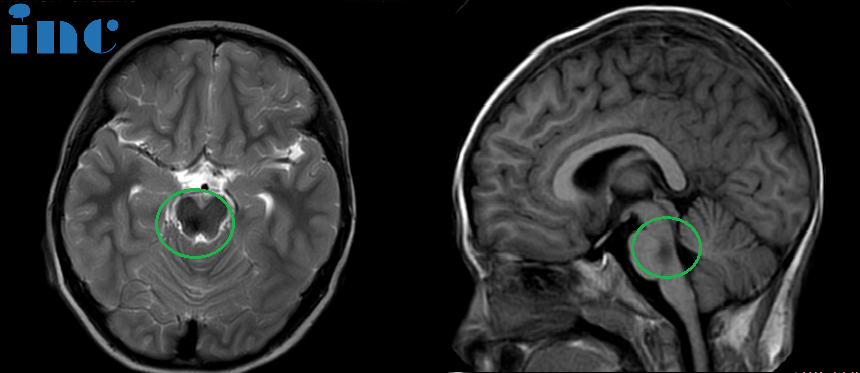

术后:头颅磁共振成像(蓝色区域)显示小脑半球及脑干形态正常,中线结构居中,原脑桥内团块状信号消失。